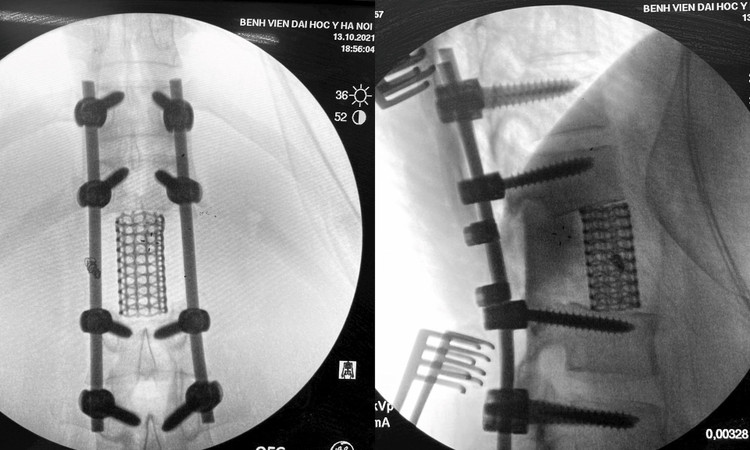

Lần đầu tiên tại Việt Nam, thay vì chỉ phẫu thuật giảm nhẹ để phục hồi và bảo tồn chức năng thần kinh, các bác sĩ Bệnh viện Đại học Y Hà Nội đã tiến hành lấy bỏ toàn bộ đốt sống, bao gồm trọn vẹn thân đốt sống chứa u và cung sau để điều trị triệt căn cho người bệnh.

May mắn, sau 7 giờ phẫu thuật căng thẳng, kíp phẫu thuật đã lấy bỏ toàn bộ cấu trúc cột sống bệnh: Cung sau bao gồm mỏm ngang, diện khớp trên dưới và mỏm gai; kèm toàn bộ thân đốt sống L1. Khối u kèm thân đốt đã được lấy triệt để toàn bộ.

Sau mổ bệnh nhân có cải thiện rõ rệt về cơ lực cũng như khả năng kiểm soát chức năng bàng quang. Chỉ đến ngày thứ 3, bệnh nhân đã ngồi được dậy và đi lại.

Các nghiên cứu nước ngoài ghi nhận thời gian cho những ca mổ thế này dao động từ 11 - 14 tiếng, lượng máu mất trung bình 1.400ml. Trong ca mổ này, thời gian phẫu thuật còn 7 tiếng, lượng máu mất chỉ hơn 600ml" - ThS.BSNT Trần Trung Kiên